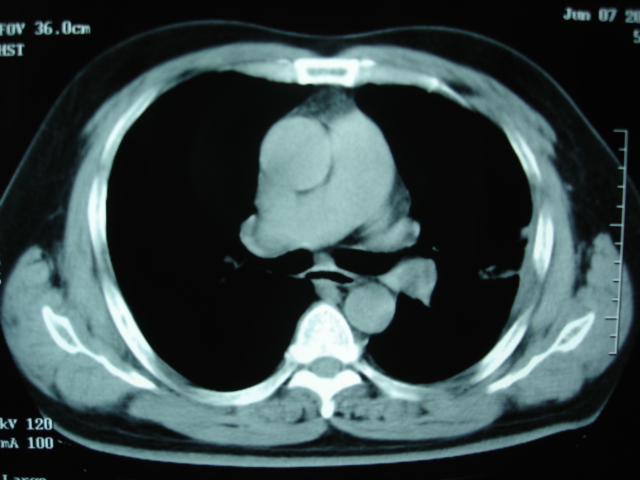

第二次ct2009.6.7 住院后ect未见异常,查痰(阴性)大量抗菌素抗炎一个月后病灶明显变小,7月5号出院后回家后口服抗菌素45天

第三次ct2009.8.21

炎症,最厚一次已吸收

考虑左肺上叶炎症感染(炎性假瘤可能)。

考虑 左肺上叶炎症感染 [炎性假瘤可能性大]。

不排除肺癌